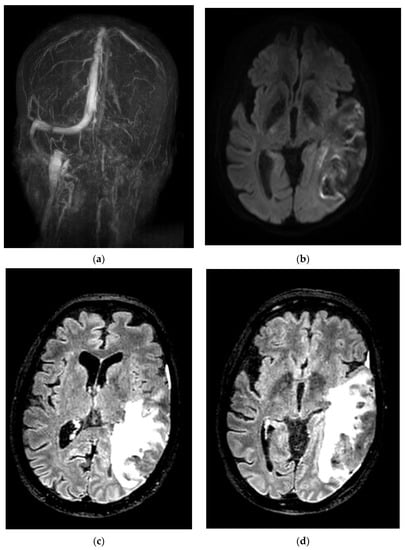

| F | 52 | Yes (Astra Zeneca) | 5 miscarriages, SAPL-negative | 18 | Right lateral and sigmoid sinus thrombosis | LMWH then apixaban | None | Discharged with no complications |

| F | 31 | No | No | 30 | Right lateral sinus and superior sagittal sinus thrombosis | LMWH | None | Discharged with no complications |

| F | 31 | No | Oral contraceptive, anemia Hb 7 g/dL | 30 | Right lateral and sigmoid sinus thrombosis | LMWH followed by Dabigatran | None | Discharged with no complications |